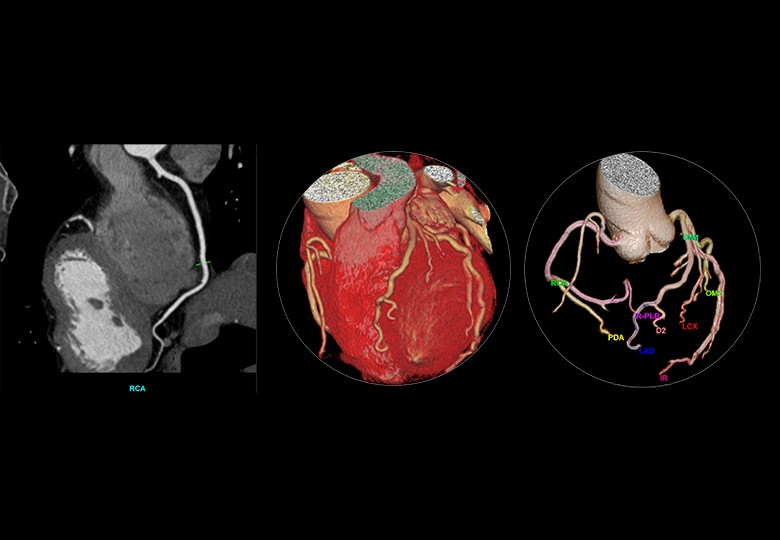

Album d'images cliniques

• Coronaire